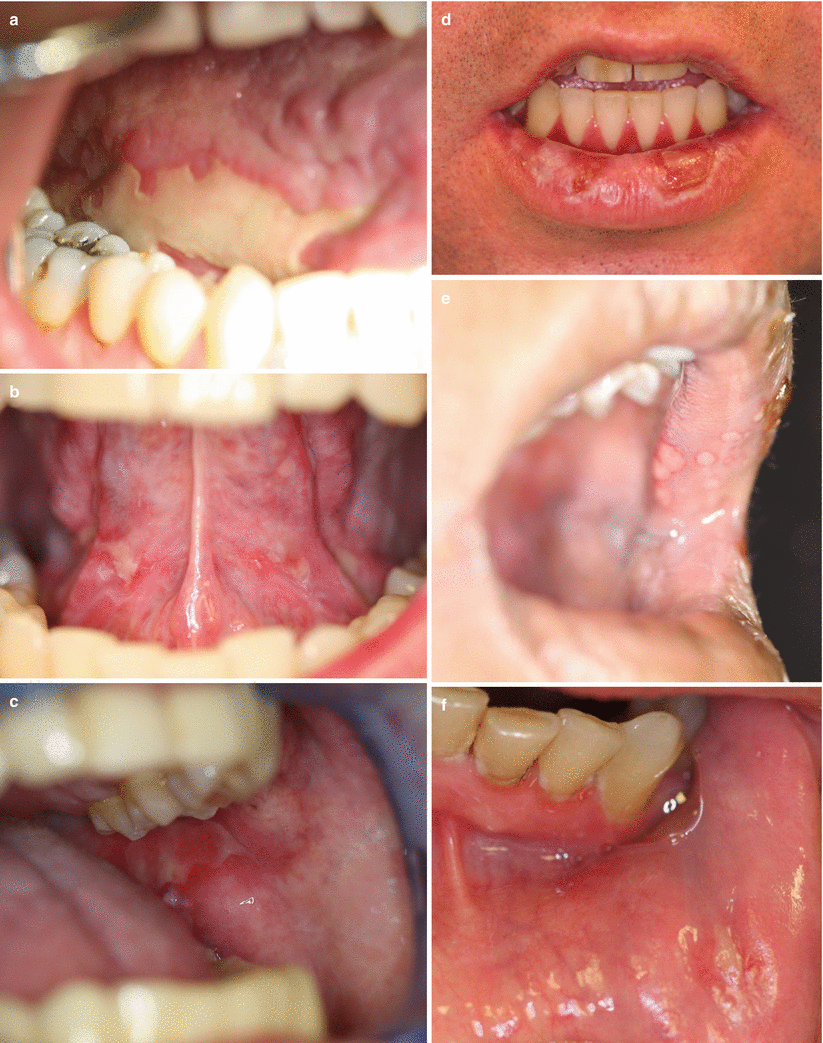

Fig. 4.2

Diagnostic and distinctive features of oral GVHD. Chronic GVHD may be clinically diagnosed by the presence of lichen planus–like hyperkeratosis on the oral mucosa in a patient who has undergone stem cell transplantation. (a) Chronic GVHD may present as white reticulate, hyperkeratotic plaques on the buccal mucosa. (b) Erythema, hyperkeratotic plaques, and pseudomembranous ulceration may be observed in chronic GVHD. Acute GVHD may have a similar ulcerated presentation with mild erythema and without hyperkeratotic plaques. (c) Mucocutaneous candidiasis, presenting here as white plaques on the posterior soft palate and anterior pillar of fauces (arrows) and yellow-coated tongue, can mimic acute or chronic GVHD but is generally accompanied by a burning sensation relieved with topical and systemic antifungal therapy

Fig. 4.3

Oral ulcerations in post-transplant patients. Ulcerations may occur at any site on the oral mucosa, including the roof of the mouth, buccal mucosa, tongue, gingiva, vestibules, and lips. Establishing a clear diagnosis is critical for successful treatment. Ulcers may result from GVHD, viral infection, systemic medications or other causes. (a) Acute GVHD may present as mucositis involving any site on the oral mucosa (Photo courtesy of Robert Range, DDS). (b, c) Pseudomembranous ulcerations in chronic GVHD occur in many forms, and may eventually lose their pseudomembranous covering. Common sites include the base of the ventral tongue and the buccal mucosa. (d) Chronic GVHD may present on the cutaneous lip as wide, irregularly shaped ulcers in the setting of white lacy lesions, chapping, or generalized superficial hyperkeratosis of the cutaneous lip. (e) Ulcerations on the cutaneous lip may also be caused by viruses, including herpes simplex virus (HSV). HSV presents as clustered vesicles that, when unroofed, leave punched-out ulcerations. (f) Sirolimus, and less frequently other mTOR inhibitors, may induce isolated painful oral ulcerations, mucositis, or stomatitis. These findings typically occur in the setting of supratherapeutic serum drug levels and resolve with adjustment of drug dose. Palliative care may be required to help reduce oral pain until resolution of the ulcers